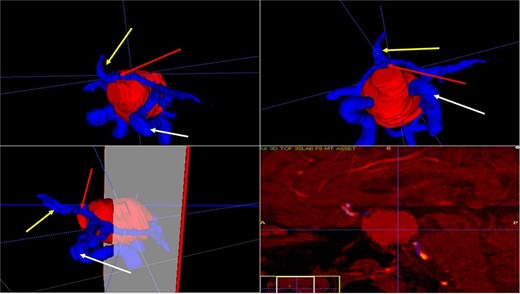

3D reconstruction through manual planimetric segmentation of the tumor and its vascular relationships. White arrow, left internal carotid artery. Yellow arrow, anterior cerebral artery segment A2. Red arrow, anterior communicating artery.

A 71-year-old woman who gradually began with bitemporal hemianopia, progressing to amaurosis of the right eye, adding diabetes insipidus. An MRI study obtained the following images (Fig. 1). 3D reconstruction was performed by manual segmentation to obtain the anatomy of the tumor and its vascular relationships. For this segmentation, it was necessary to splice T2, T1, Contrast, and 3D TOF sequences (Fig. 2). The importance of the reconstruction lies in being able to adequately observe most of the cerebral blood circle and its relationships with the tumor. At the time of carrying out the transnasal resection surgery and keeping in mind the proximity of the anterior communicating artery with the dorso-ventral region of the tumor, the capsule was resected with excessive caution to avoid generating excessive traction and thus avoiding injuries—important vascular (Fig. 3).